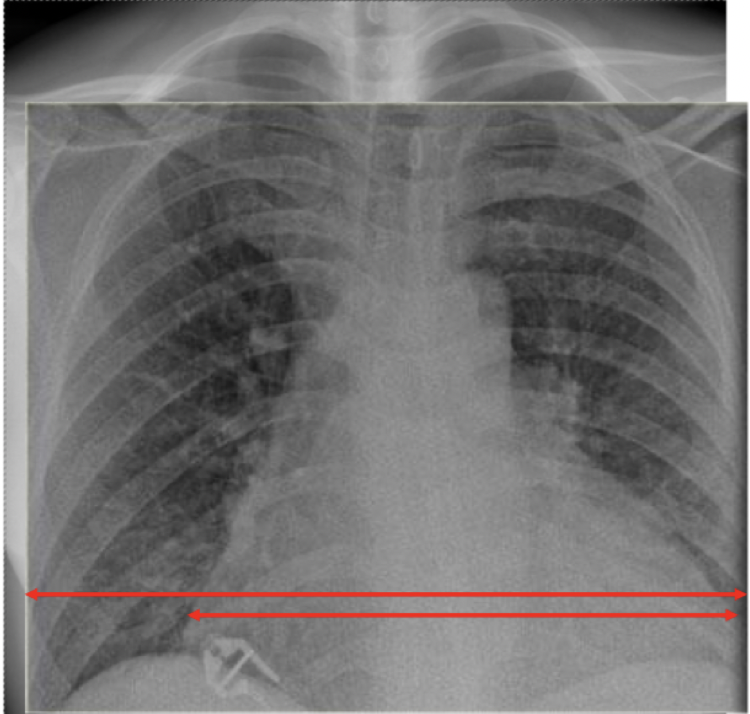

Hvordan kan man se om et hjerte er forstørret v.b.a. rtg. thorax?

Et hjerte er normalt stort hvis hjertes diameter er < 50% av thorax-diameter